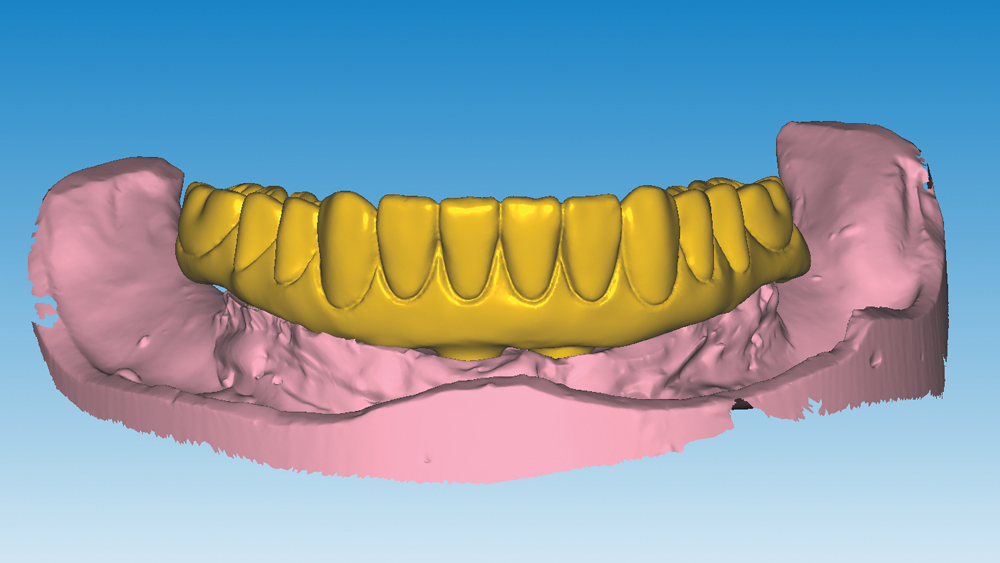

This patient was unhappy with the esthetics of her existing upper denture as well as the discomfort and instability caused by her loose-fitting mandibular partial denture. Although her concerns with the maxillary denture could be addressed with a new, more esthetic appliance, she preferred implant treatment for her mandible, where a fixed solution was needed to adequately restore function, stability and comfort.

The patient’s remaining mandibular teeth were extracted followed by immediate implant placement and delivery of a fixed provisional appliance. After integration of the implants, the prosthetic designs for the new upper denture and lower implant restoration were determined in tandem. Ultimately, the dual-arch restorations addressed the functional and esthetic challenges of the case while staying within the financial means of the patient, demonstrating the benefits of a flexible, multifaceted approach to restorative dentistry.